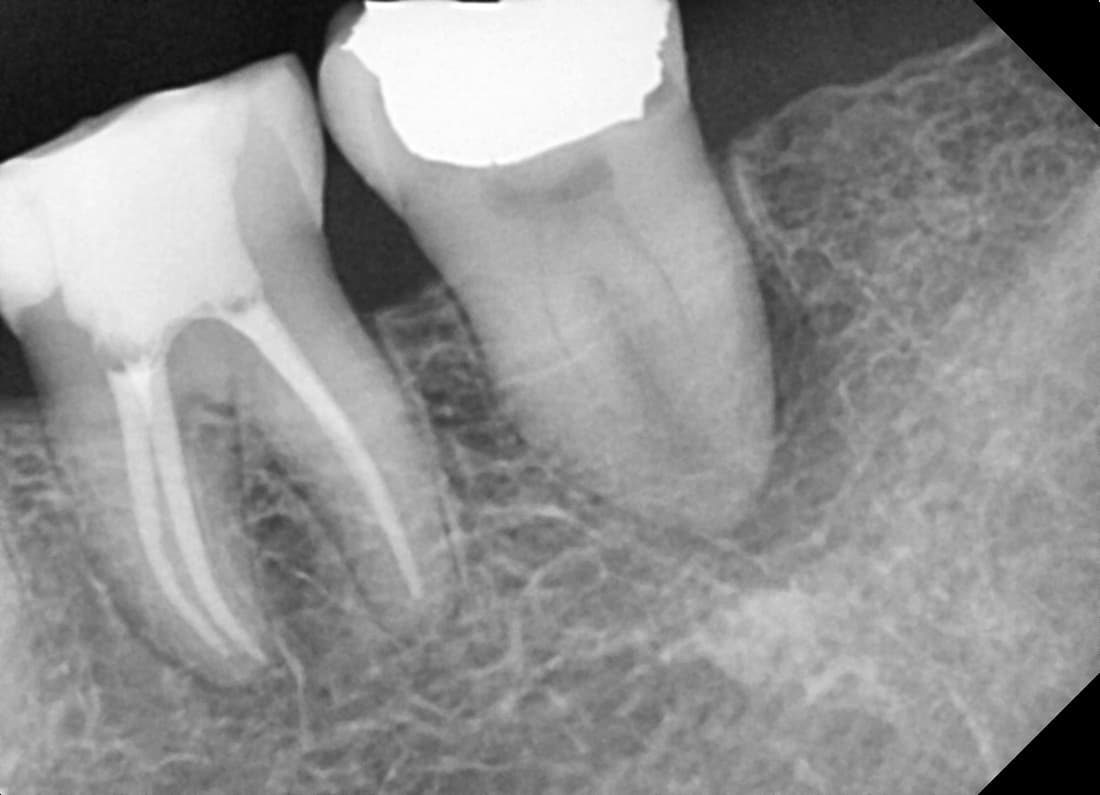

치근단병소 치유

뿌리 끝 염증으로 발치 권유받은 어금니

Before

After

신경치료 1년 2개월 후 치근단병소 완전 치유